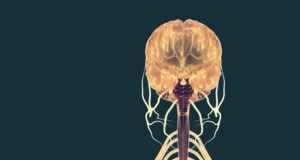

Image: Anatomy Insider/Shutterstock